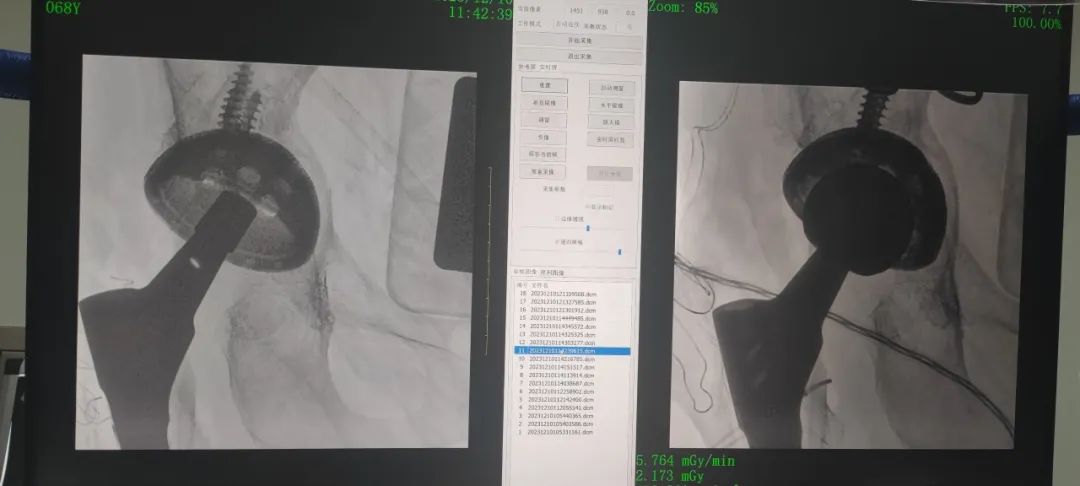

關(guān)節(jié)外科劉健安主任團隊經(jīng)認真完善輔助檢查、充分討論后,詳細制定手術(shù)計劃并成功完成了三院建院以來首臺復(fù)雜髖關(guān)節(jié)不穩(wěn)重建翻修手術(shù),術(shù)中選取愛康多孔ACT臼杯、wagner sl 股骨柄,術(shù)后患者恢復(fù)良好,假體穩(wěn)定性良好,患者非常滿意。

圖3-術(shù)中透視情況